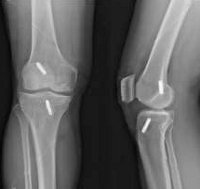

Рентгенография коленного сустава

Рентген коленного сустава. Метод лучевой диагностики применяется для оценки состояния коленного сустава. При травмах его назначают при подозрении на перелом мыщелков, мыщелков и бугристость большеберцовой кости, перелом головы и шеи малоберцовой кости, перелом и вывих надколенника. В других отраслях медицины он используется для лечения аномалий развития, опухолей, дистрофических дистрофических заболеваний и воспалительных заболеваний. Стандартное исследование проводится в двух проекциях (правой и боковой). Не требуется обучение Процедура не рекомендуется для детей и беременных женщин.

В травматологии рентгенограммы коленного сустава назначают при переломах бугристости и мыщелков большеберцовой кости, переломах шейки и головки малоберцовой кости, переломе мыщелка бедренной кости, вывихе и переломе бедренной кости. коленная чашечка. В ортопедии методика используется в процессе диагностики остеоартроза и аномалий развития. В ревматологии показаниями процедуры являются боль и отек колена при ревматоидном артрите и других заболеваниях. В онкологии исследование проводится при подозрении на злокачественную или доброкачественную опухоль дистального отдела бедра, проксимального отдела малоберцовой кости и большеберцовой кости.